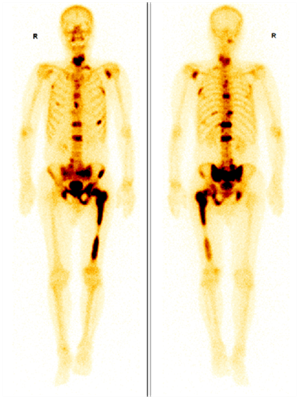

全身骨顯像(Whole Body Bone Scan,WBBS),又稱為骨掃描,是將放射性核素標(biāo)記的顯像劑(一般為99mTc-MDP)注射到體內(nèi),顯像劑隨血流到達(dá)全身骨骼,通過離子交換、化學(xué)吸附和與骨的有機(jī)成分結(jié)合的方式沉積到骨骼中,利用單光子發(fā)射型計(jì)算機(jī)斷層掃描儀(SPECT)得到顯像劑在全身骨骼分布情況,從而得到全身骨骼的圖像。

圖示,前列腺癌多發(fā)骨轉(zhuǎn)移,圖中深顏色區(qū)域?yàn)檗D(zhuǎn)移灶。